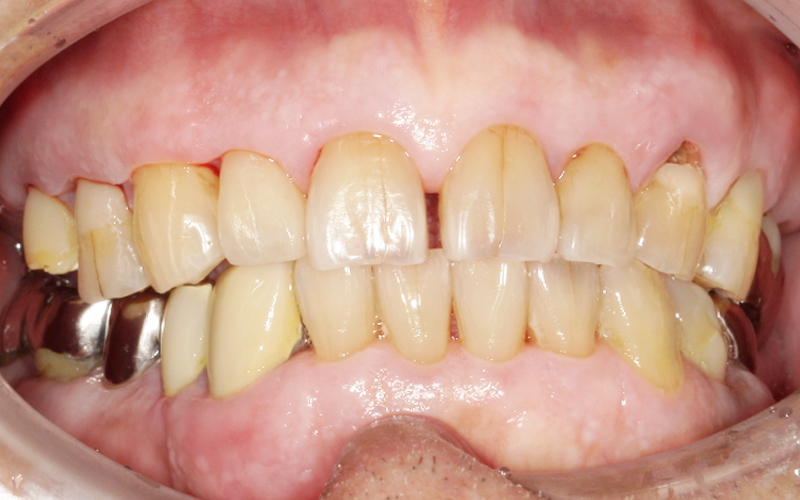

今回の患者様は左下の被せ物が取れたとのことで来院されました。 |

痛みはありませんが、歯は黒くなっていて虫歯が拡がっています。レントゲンを撮ってみると、 |

|---|

中はこの様な具合になっていました。 |